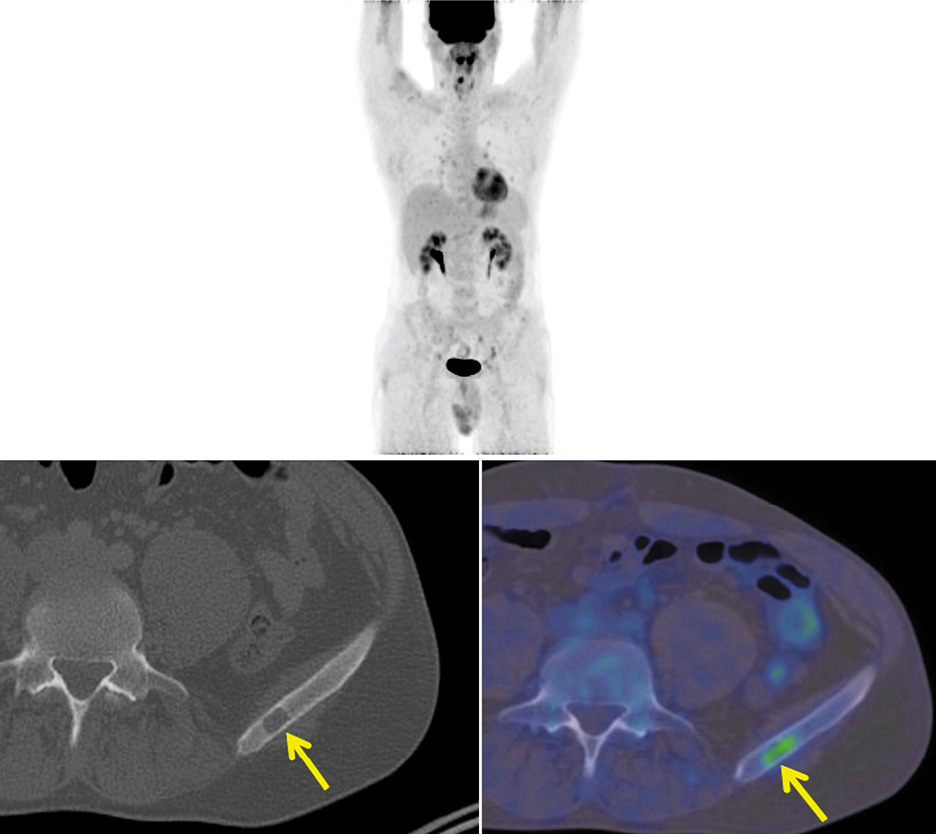

Учитывая характер течения заболевания, с целью уточнения распространенности опухолевого процесса больному выполнена позитронно-эмиссионная томография, совмещенная с компьютерной томографией (ПЭТ/КТ) с 18-фтордезоксиглюкозой (18-ФДГ). При этом в крыле подвздошной кости слева выявлен очаг литической деструкции размером 12×8 мм, кортикальная пластинка истончена, прослеживается без нарушения целостности. Коэффициент максимального накопления радиофармпрепарата SUVmax равен 2,0 (рис. 1).

Рис. 1. Больной С., 43 года. На аксиальной КТ- и совмещенной ПЭТ/КТ-проекциях в крыле подвздошной кости слева определяется очаг литической деструкции размером 12×8 мм с диффузно повышенной фиксацией РФП, SUVmax 2,00 (стрелка).